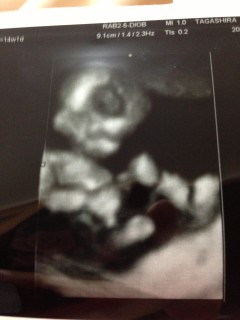

初めて旦那も一緒に産婦人科へ(*^o^*) 緊張してたのかガチガチ!笑 べびたんはしゃっくり連発しながら 足を曲げたり伸ばしたり(*^^*) 心臓もちゃんと動いてたし 問題も無さそうだったので ひとまず安心(*^^)v 次は3週間後(^O^) 性別分かるかな?笑 次回が楽しみ♪

前回受診した時に比べて、大きくなっているし手足が長くなってるみたい。2wちょっと分くらい大きめの我が子。早く性別が知りたいなぁ。。